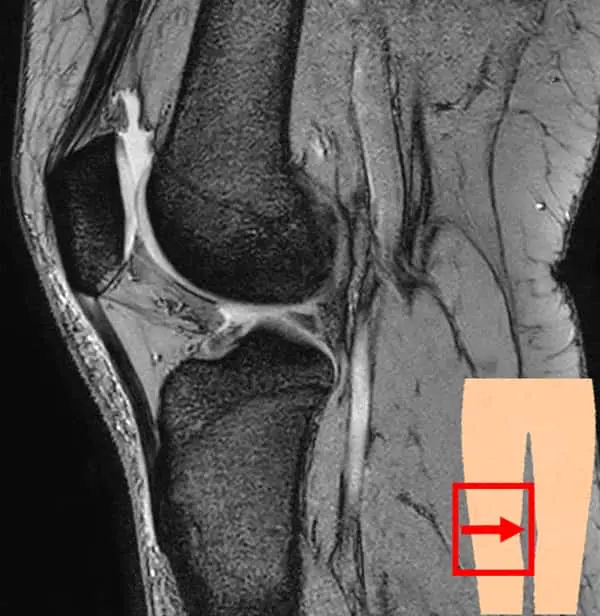

膝関節は大腿骨(太ももの骨)と脛骨(すねの骨)、腓骨(脛骨の外側にあるすねの骨)、膝蓋骨(膝のお皿)から構成されています。これらの骨を靱帯や筋肉、腱で繋いでおり、それらによって安定性を保っています。

膝関節の検査では、レントゲンの検査が一般的ですが、当クリニックではMRIを使用した検査を行なっています。

レントゲンよりも骨の内部や軟骨、半月板・靱帯の状態を把握できます。また、炎症や水が溜まっているかなどの確認も可能です。レントゲンとは違い、放射線被ばくもなく検査ができますので、体への負担が気になる方にもおすすめです。